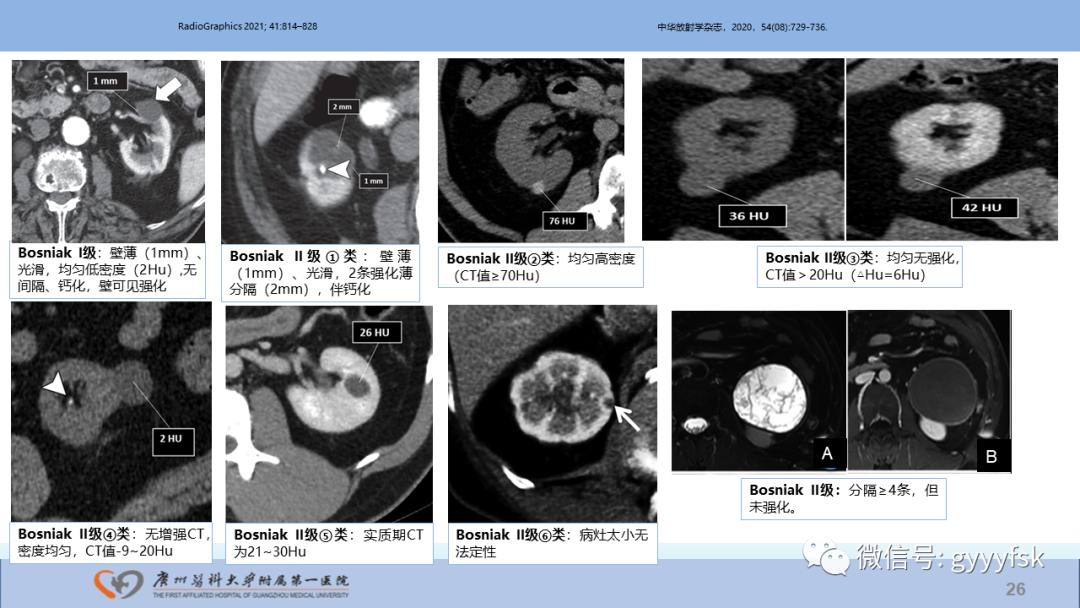

【PPT】肾癌相关影像诊断的文献汇报-26